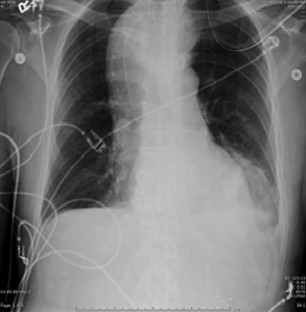

Fig. 1